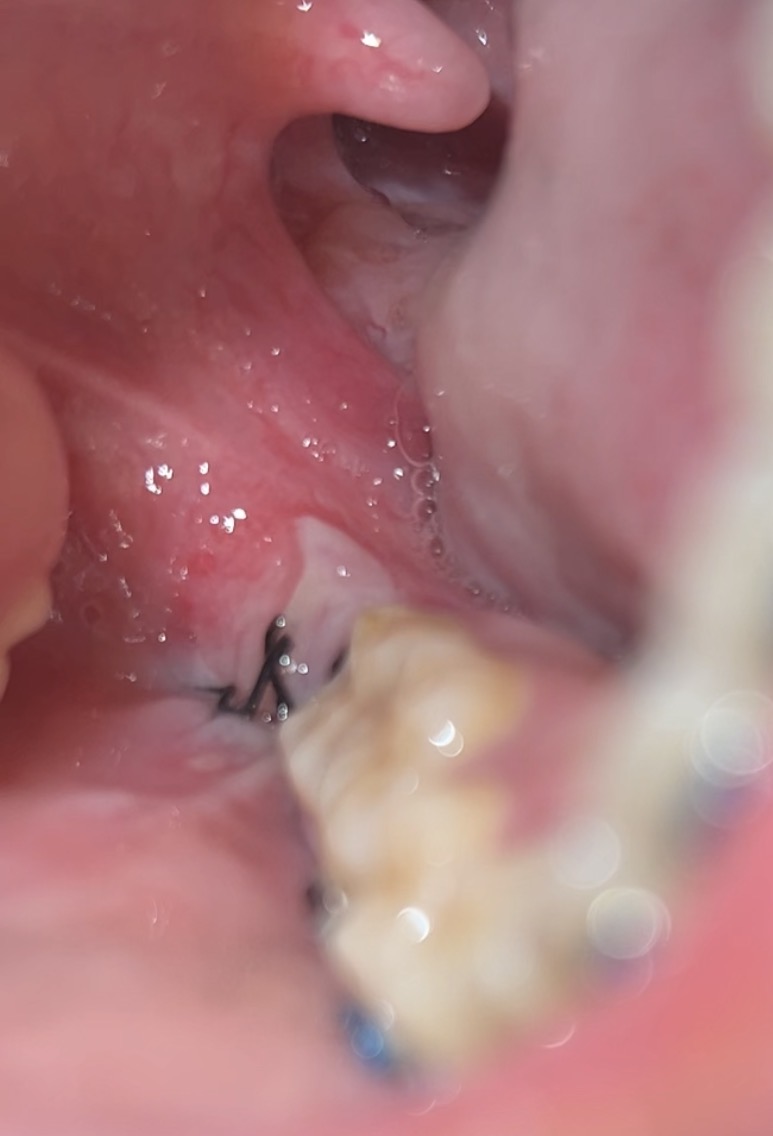

ผ่าฟันคุดมาแล้วมีวงสีขาวๆ ปกติไหมคะ?

คือผ่าฟันคุดมาได้1วัน ปวดหนักแค่วันแรก วันที่2ไม่ค่อยปวด กินได้ปกติ พอมาเช็คตอนเย็น สรุปไหมขาดค่ะ บวกกับมาเจอวงสีขาวๆตกใจมาก แบบนี้คือปกติไหมคะ แต่ไม่ได้มีอาการปวดมากเหมือนวันแรก